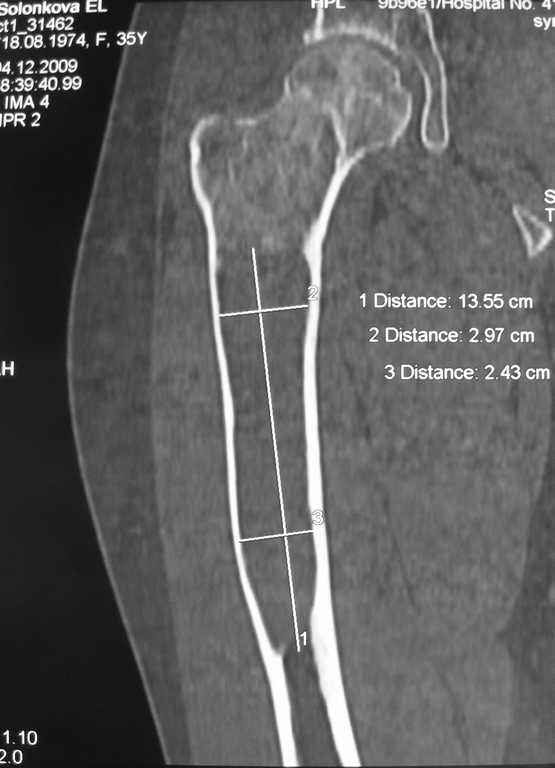

При наличии в института сосудистых хирургов, как альтернативный метод можно было бы предложить графт как показано на снимке.

Не мой случай, но красиво!